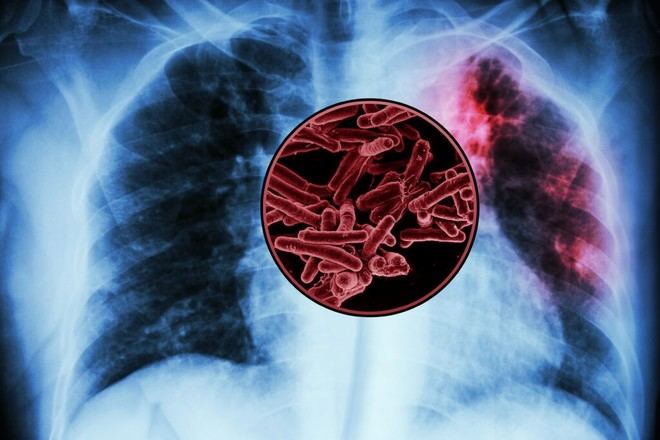

Un estudio reciente realizado por un equipo de ingenieros biológicos del MIT ha identificado varios antígenos que podrían ser utilizados para desarrollar una nueva vacuna contra la tuberculosis, considerada la enfermedad infecciosa más mortal del mundo. Este avance se basa en un análisis exhaustivo de más de 4,000 proteínas bacterianas asociadas a la tuberculosis.

Los investigadores lograron identificar un grupo selecto de péptidos inmunogénicos que parecen provocar una respuesta robusta en los linfocitos T, células clave en la orquestación de la respuesta inmune frente a infecciones. Actualmente, solo existe una vacuna para la tuberculosis, conocida como BCG, que es una versión atenuada de la bacteria causante de esta enfermedad en vacas. Aunque se aplica ampliamente en algunas regiones del mundo, su eficacia es limitada, especialmente en adultos con tuberculosis pulmonar. Cada año, esta enfermedad cobra más de un millón de vidas a nivel global.

A lo largo de más de un siglo desde el desarrollo de la BCG, no se han aprobado nuevas vacunas contra la tuberculosis. La bacteria Mycobacterium tuberculosis produce más de 4,000 proteínas, lo que complica enormemente la tarea de seleccionar aquellas capaces de inducir una respuesta inmune efectiva si se utilizan como vacunas.